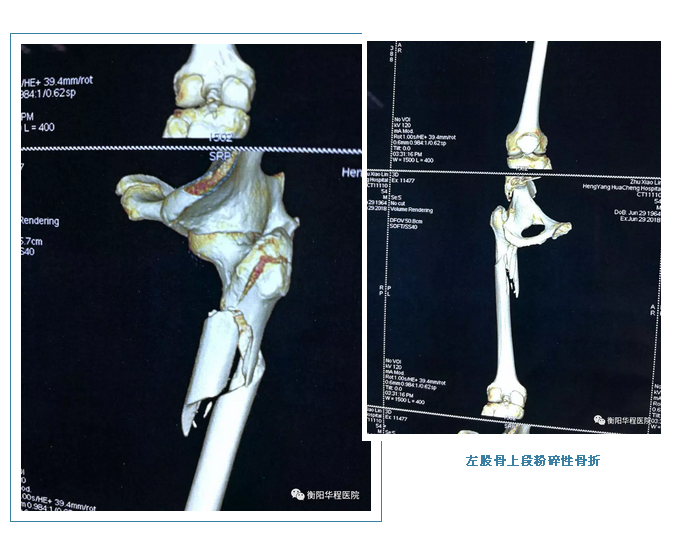

6月29日,59歲的祝某(化名)因不慎從貨上摔落,當(dāng)時(shí)祝某明顯感到左大腿劇烈疼痛,動(dòng)彈不得,妻子著急萬分,立刻帶祝某到骨科專科醫(yī)院救治,因其妻子覺得醫(yī)院住院條件差,不愿入住其??漆t(yī)院,遂后通過聯(lián)系我院120急救中心,由救護(hù)車接入我院,以“左股骨上段粉碎性骨折”收住我院骨科中心。

入院后,祝某這一情況是適于保守治療還是手術(shù)治療?如果保守治療,那么并發(fā)癥也將隨之而來;如果用傳統(tǒng)的手術(shù),其患者的恢復(fù)期會(huì)比較漫長,骨科中心主任劉剛飛、副主任馮建立帶領(lǐng)的團(tuán)隊(duì)一起為祝某作了系統(tǒng)科學(xué)的患者手術(shù)風(fēng)險(xiǎn)評(píng)估。經(jīng)家屬同意,制定了祥細(xì)而周密的手術(shù)計(jì)劃,在充分準(zhǔn)備后,由劉剛飛主任主刀,為祝某做了“左股骨上段粉碎性骨折切開復(fù)位髓釘內(nèi)固定術(shù)(PFNA)”,在歷經(jīng)1個(gè)多小時(shí)后,手術(shù)順利完成。術(shù)后經(jīng)過醫(yī)護(hù)團(tuán)隊(duì)的悉心照料,患者恢復(fù)良好,其妻子懸著的一顆心漸漸放下。